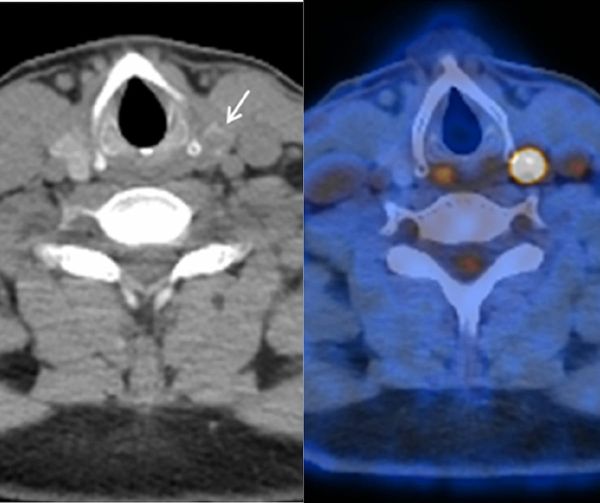

Can PET/CT Bolster Malignancy Detection with Thyroid Incidentalomas?